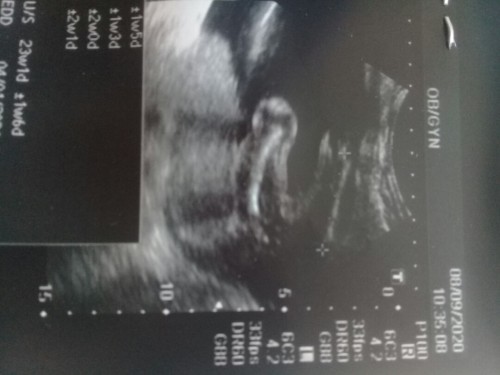

23+2เเล้วคะเเม่ 😍

น้องน่าจะ ญ.น่ะแม่

น่าจะหญิงนะคะ

น่าจะหญิงค่ะ